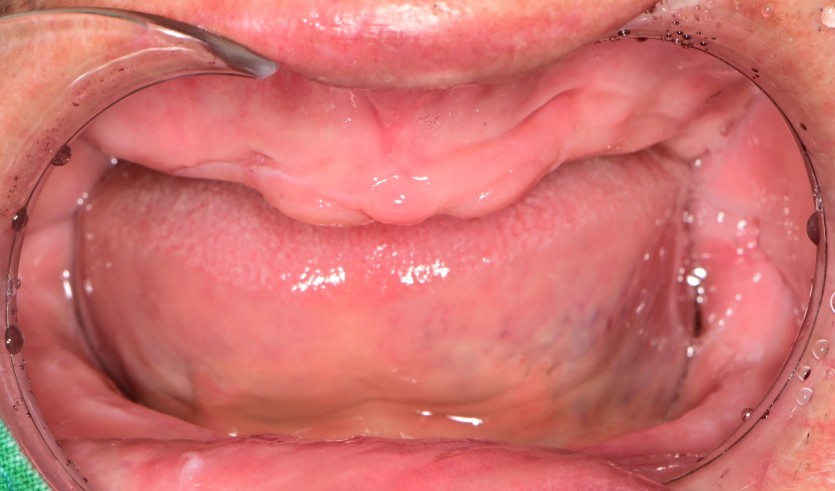

만 61세 전체 임플란트 증례(하악 풀아치)

전체 임플란트 증례입니다.

14개의 임플란트로 완성하였습니다.(하악 풀아치 진행)